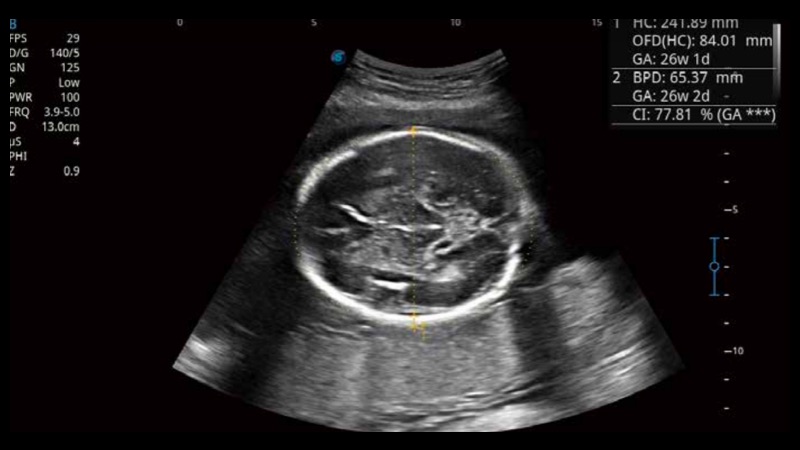

S-Fetus基于大数据深度学习算法,能够帮助您在产前筛查过程中智能识别胎儿标准切面、自动测量并录入报告。一个按键,即可智能、精准、高效地获取胎儿生理指标,极大简化您的产科检查操作。

可快速对产科扫查切面完成胎儿生理学参数的自动测量,减少操作者按键次数,大幅提升检查效率。

自动识别颈项透明层并获得NT值,为早孕胎儿畸形筛查提供有效测量工具,提高诊断效率和诊断信心。